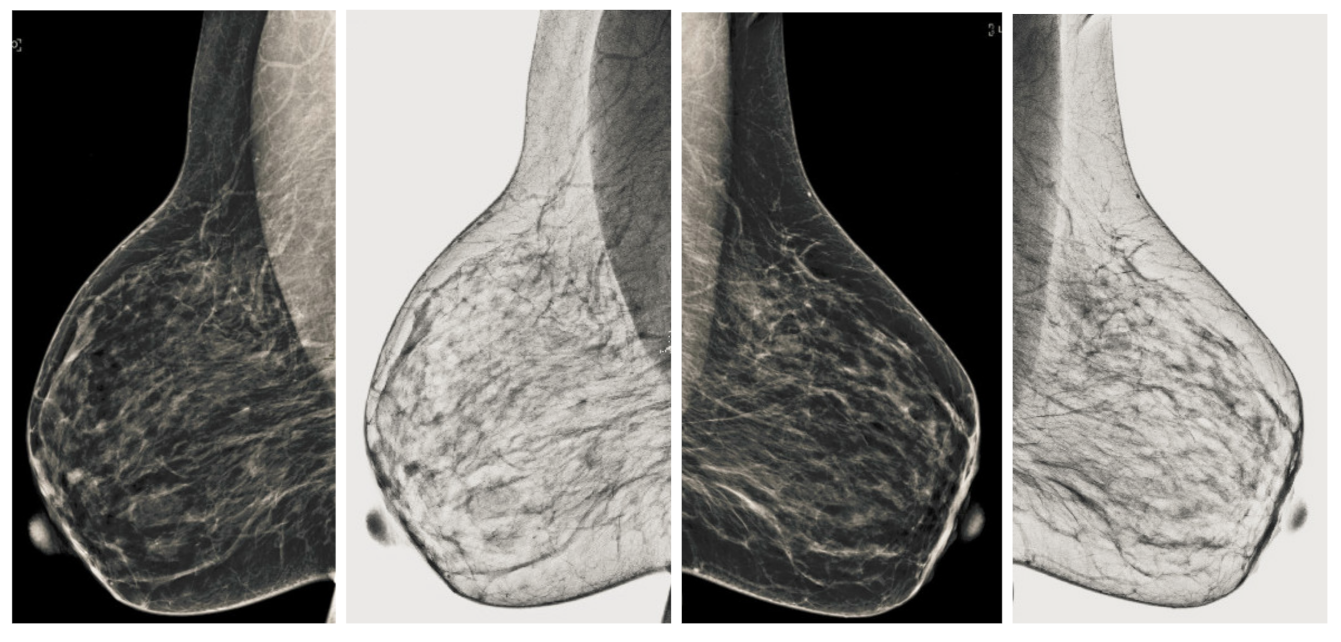

Figure 15.

Analysis of CC view of BI-RADS-5 mammogram images.

Figure 16.

Analysis of MLO view of BI-RADS-5 mammogram images.

We also measured the PSNR, the image contrast, and the EME of each category of databases, as we analyzed the image in terms of visual observation. The Table 3 shows the performance of our proposed image enhancement method. It can be seen from the Table 3 that our proposed method improved PSNR, contrast, and EME, and this also shows that our method can work on every category of BI-RADS. Because many techniques do not work on higher grade BI-RADS due to the complexity and the images are not of good quality. We obtained an average improvement in PSNR, contrast, and EME in the Table 4. For more observations, we analyzed the visual image of each category and we analyzed the CC and MLO of each category as shown in the Figure 7, Figure 8, Figure 9, Figure 10, Figure 11, Figure 12, Figure 13, Figure 14, Figure 15 and Figure 16. From the figures, every detail of image of every category can be observed, leading to better segmentation of the abnormal region. This image enhancement technique can be used as preprocessing steps for the detection of breast cancer. It is a very fast processing algorithm and it takes on 21.13 s. It gives opportunity to medical experts to analyze the mammogram images very quickly to propose the timely treatment.